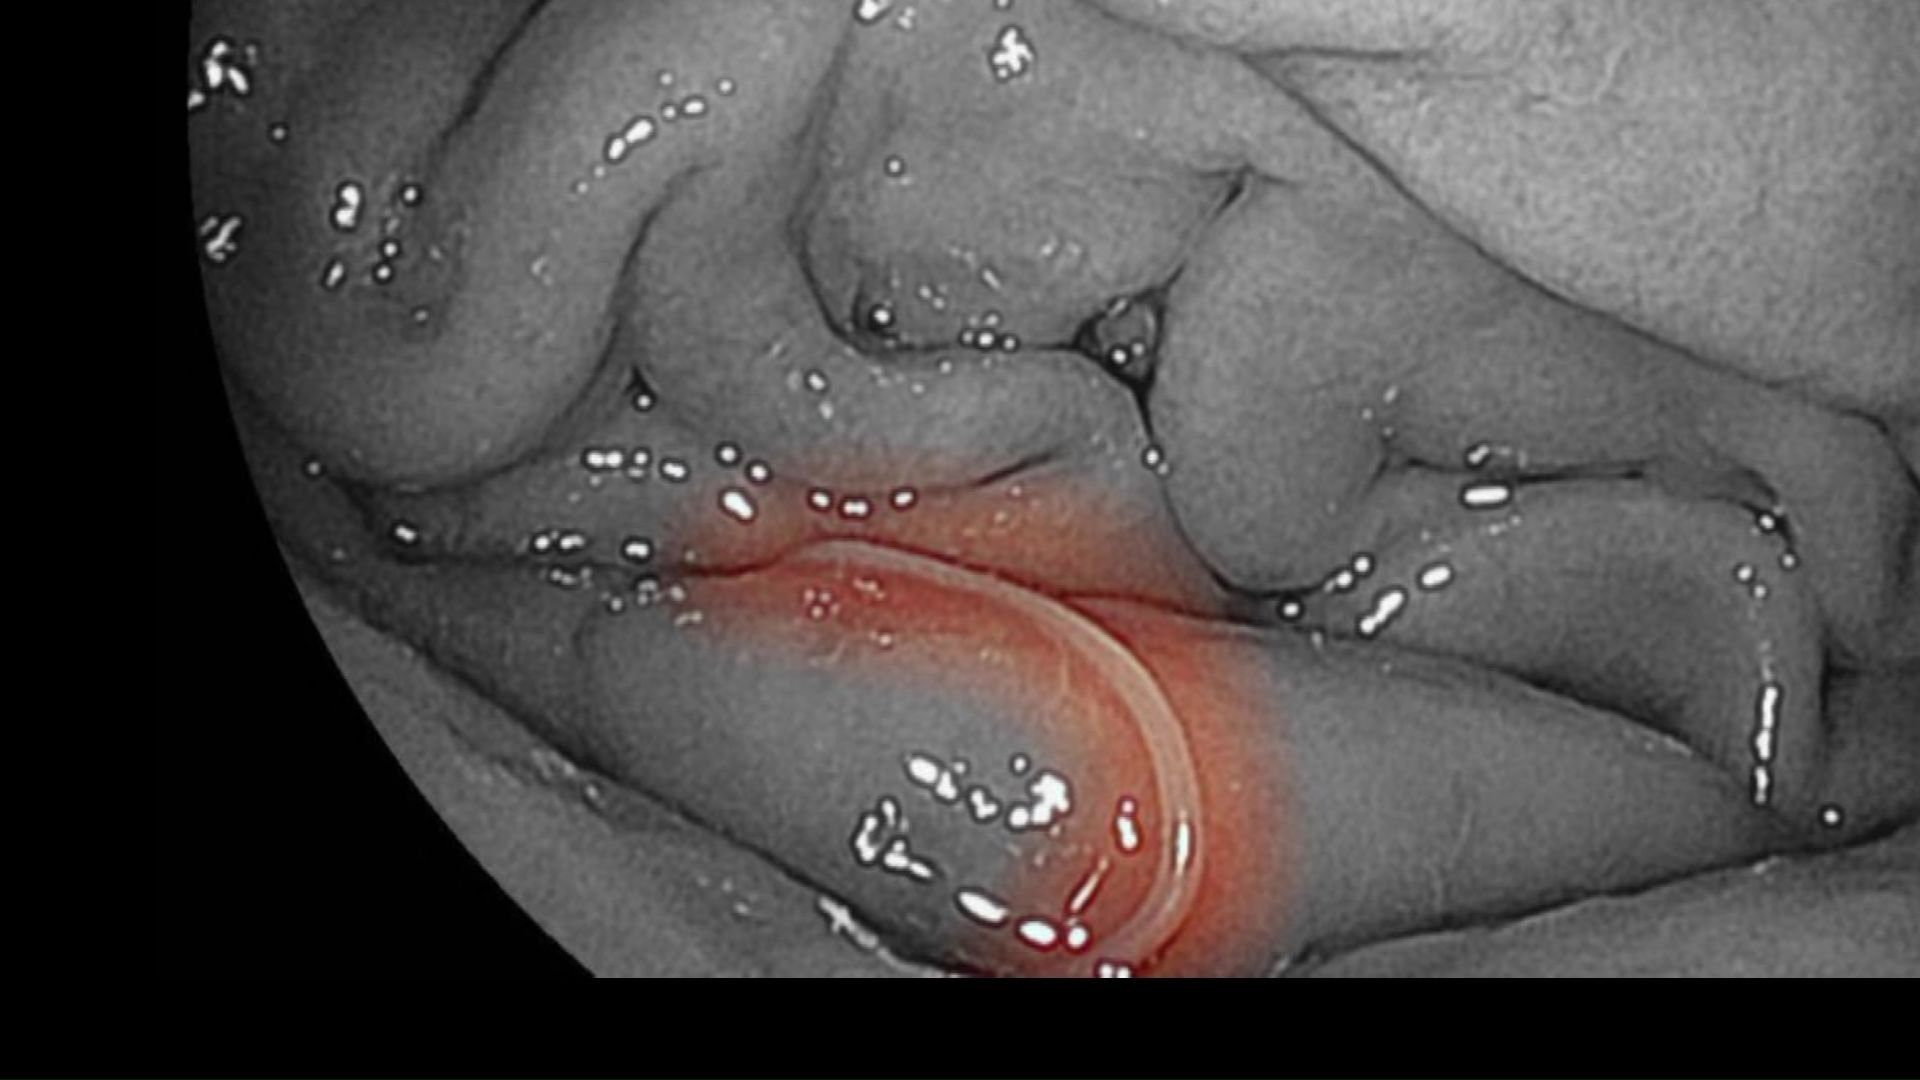

どうにか病院に行って胃カメラで検査すると、モニターに映ったのは白い糸くずのようなアニサキスでした。